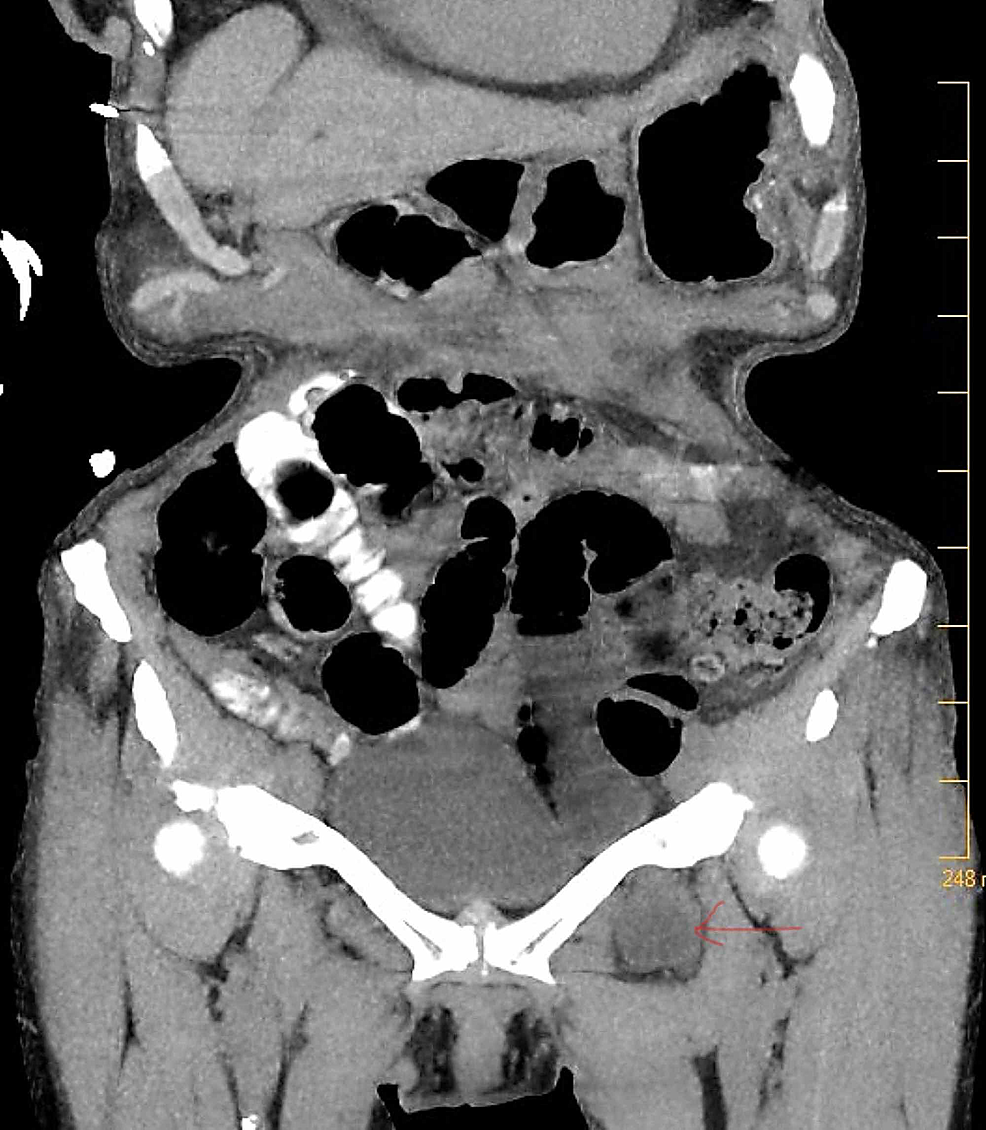

Axial Ct Image Shows Bilateral Obturator Hernias With Fluid In